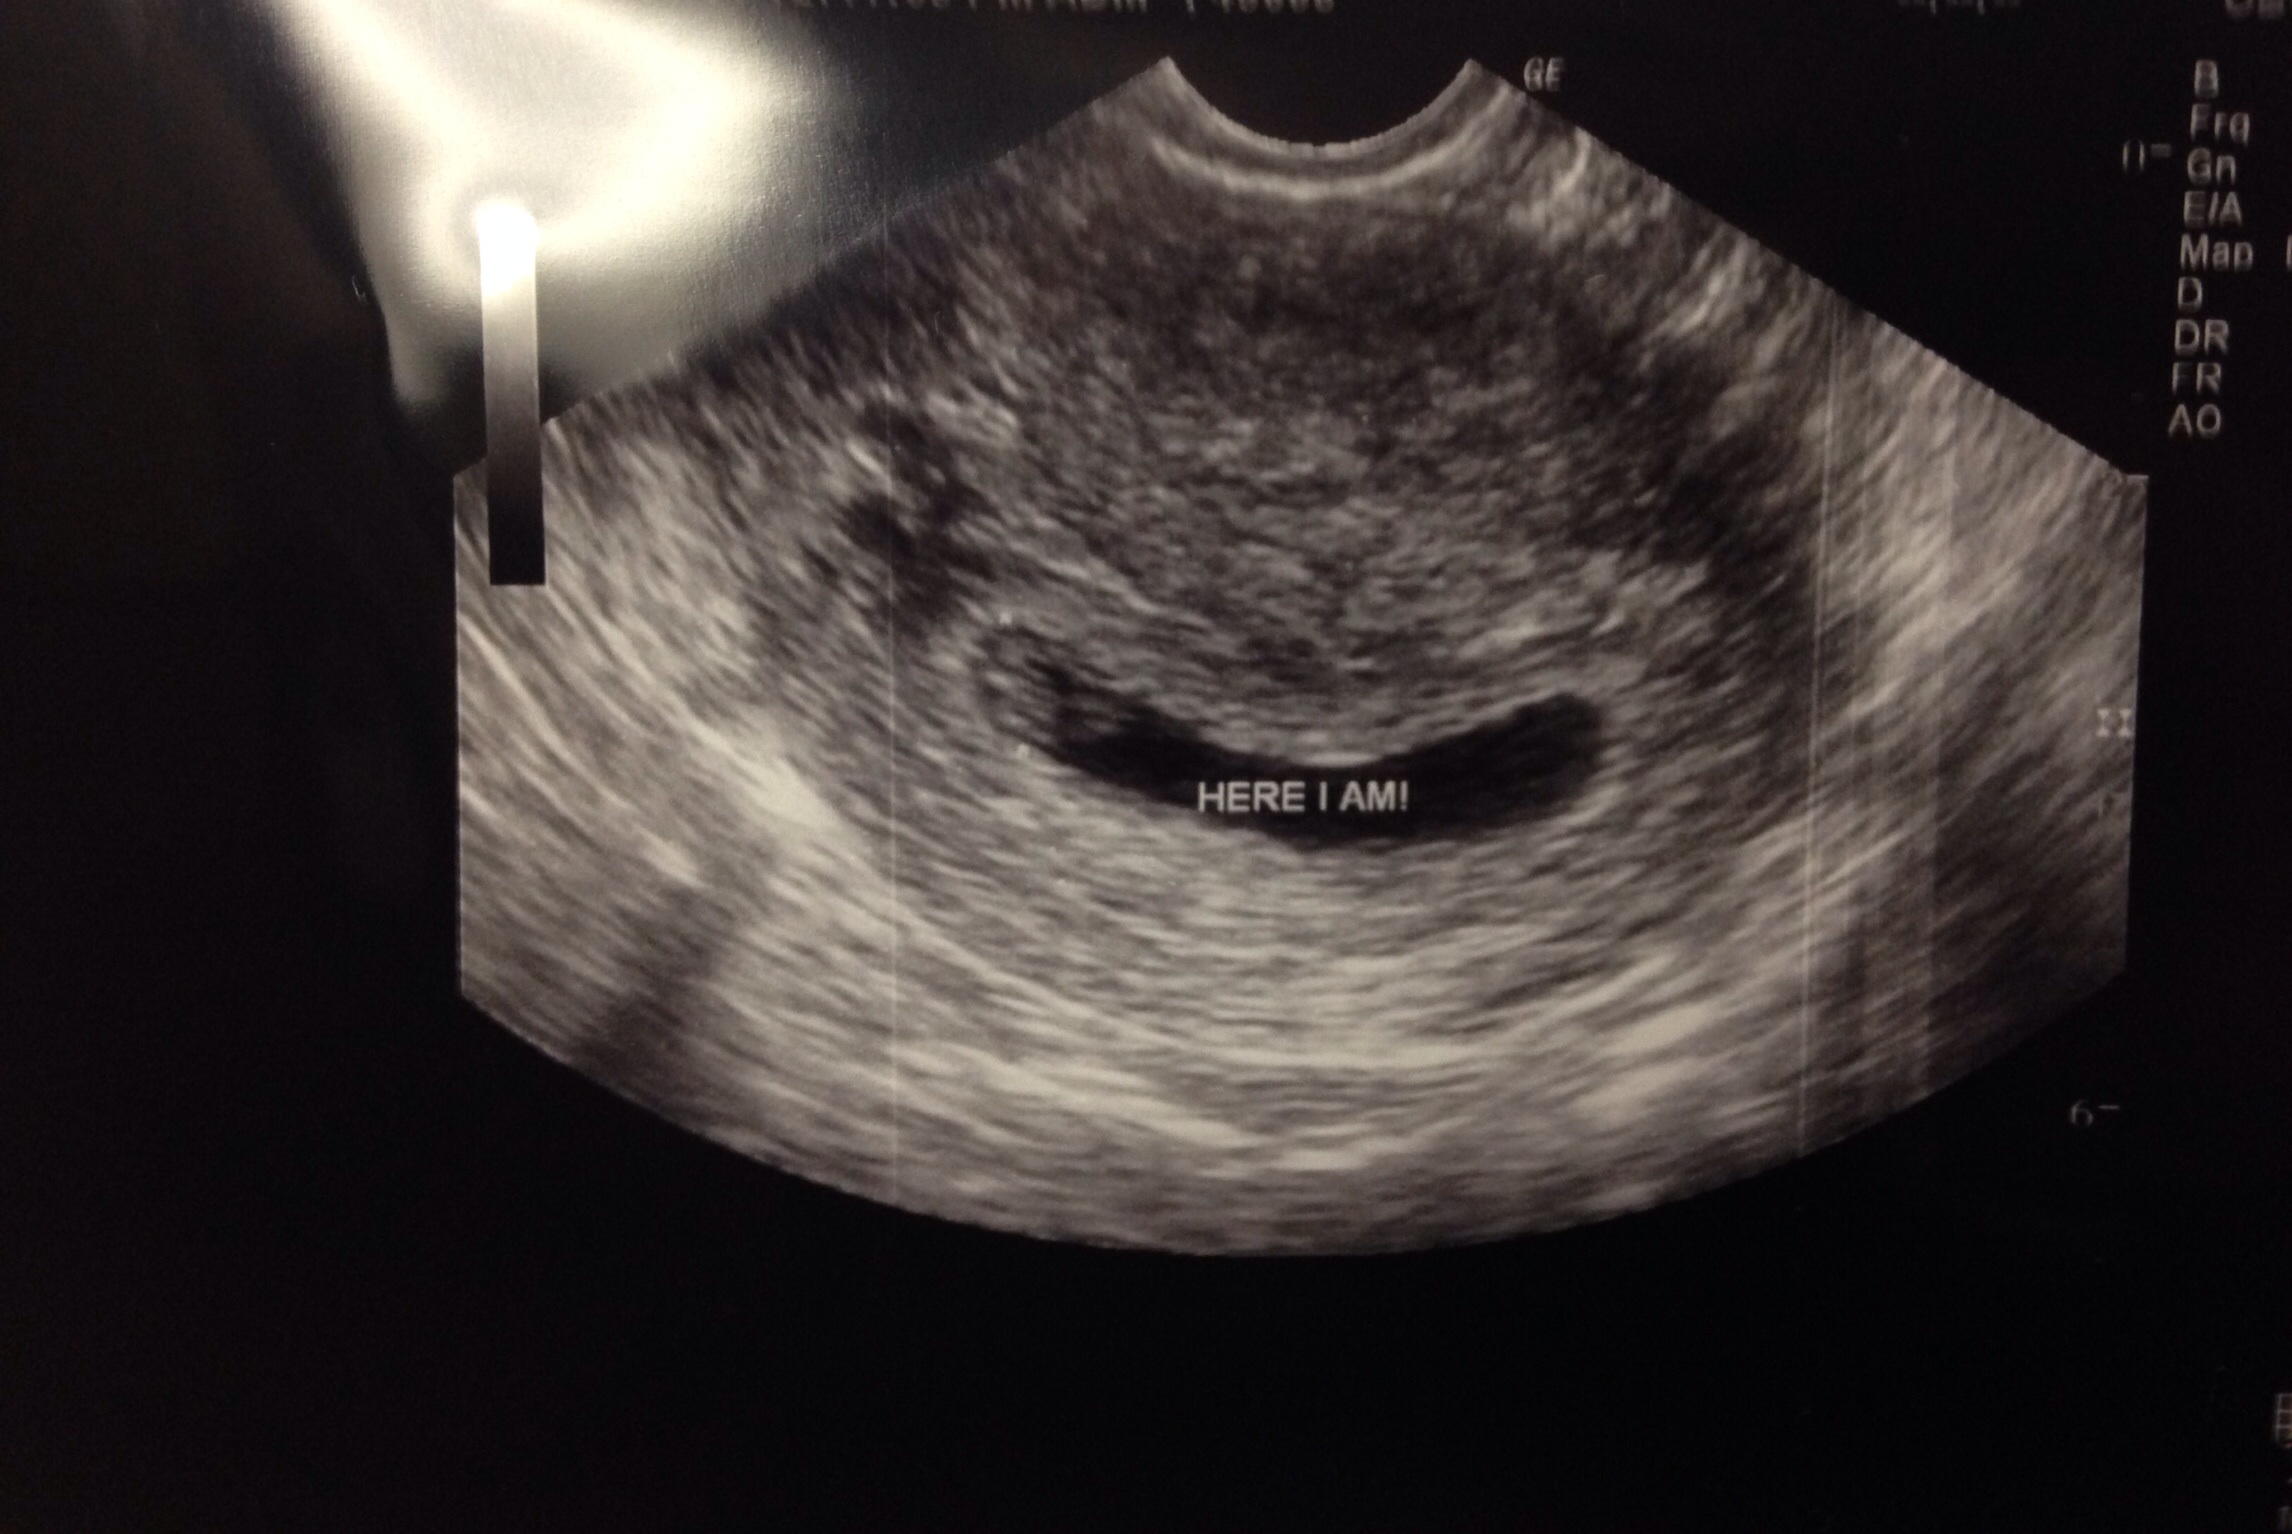

• I'm 7 weeks 2 days. Could one of the corpus luteum have absorbed? Do we agree it's two sacs? Definitely two placenta but doctor was weary to say "two sacs" since he said it was early and lining could thin. But goodness they sure do look like two separate sacs

• Where is the placenta? Now I'm confused if he showed me the two babies and two yolk sacs.. :-/